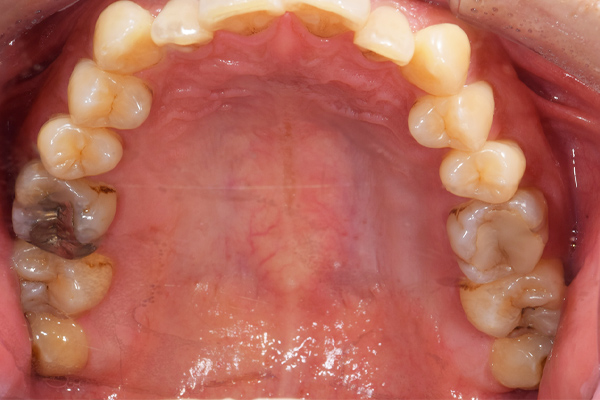

下顎の親知らずは右下のみはえています。まっすぐはえていますが、前の歯よりも低い位置にあるので、磨くのが難しそうです。舌側の歯茎がかぶっているのがみてとれます。

上顎の親知らずは頬の方を向いてはえています。こういうった親知らずはやはり磨くのがとても難しいです。